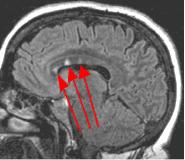

Thin-section sagittal FLAIR images increase detection of small MS plaques even further, first reported by Hashemi, et al. (Ref. 1). They also have the advantage of clearly showing the corpus callosum and subependymal regions. An early sign of MS is subependymal nodularity and subcallosal striations (Ref. 1-2), not clearly visible on axial images. Fig. 3-4 in the same patient clearly show subcallosal MS plaques (arrows) along the undersurface of corpus callosum.